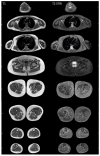

We report a case of SYNE1-associated autosomal recessive spinocerebellar ataxia (SCAR8) presenting with a complex multisystemic phenotype, including highly elevated creatine kinase levels and lower-leg muscle atrophy. In addition to identifying two novel pathogenic variants in the SYNE1 gene, whole-exome sequencing revealed three variants of uncertain significance in the DYSF gene. Electromyography and muscle magnetic resonance imaging indicated a neurogenic pattern of muscle involvement. These findings, along with the segregation analysis of the variants, allowed us to exclude DYSF-associated muscular dystrophy; however, we cannot entirely rule out the possibility that the DYSF gene variants may act as modifiers of the patient's phenotype.